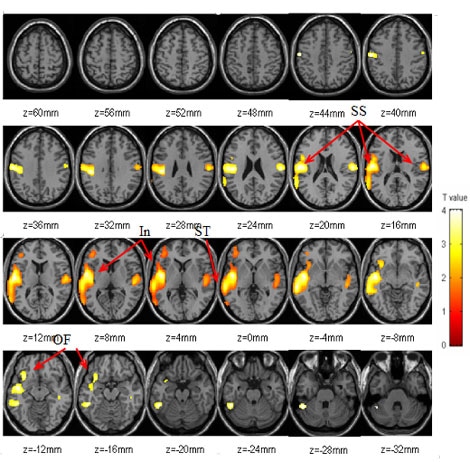

The researchers found that food stimulation significantly increased whole brain metabolism. Metabolism was higher in all regions of the brain examined, except for the occipital cortex, which controls vision and would not be affected. The areas most affected were the superior temporal, anterior insula, and orbitofrontal cortices. Food stimulation also resulted in increases in self-reports of hunger and desire for food. Increases in metabolism in the right orbitofrontal cortex were the ones that were most significantly correlated with increased reports of hunger.

This figure shows the areas of the brain that "lit up" with higher metabolism during food stimulation in the study. The colored areas are from a statistical parametric mapping (SPM) analysis of PET scans of all subjects in both the food stimulation and neutral intervention conditions of the study. These images are superimposed on MR images from one person's brain (taken from above), which are used to demonstrate correct anatomical positioning. All "lit" areas represent significant differences in metabolism between the two study conditions: white represents higher metabolism while red represents lower metabolism.

Most intriguing is that the orbitofrontal cortex (see arrows in the two lower left brain images labeled "OF") has higher metabolism. Studies at Brookhaven and elsewhere have shown that this brain region, which houses the dopamine system, is also active in addiction, reward and motivation.